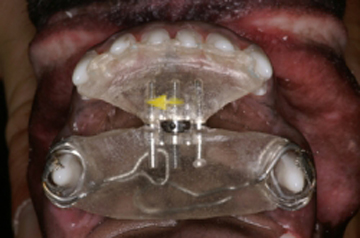

La ortodoncia es una especialidad que requiere de una capacitación muy profunda ya que la boca tiene un hueso, la mandíbula, la cual se mueve y se desplaza en movimientos de rotación y traslación tanto unilaterales como bilaterales. Cuando el médico tratante realiza un tratamiento de ortodoncia, debe saber que puede provocar una serie de trastornos que pueden dañar irremediablemente la buena oclusión del paciente al provocar interferencias oclusales y puntos prematuros de contacto. También es importante conocer cuanta es la presión que debe ejercerse por diente ya que una fuerza exagerada puede provocar la resorción de la raíz del diente provocando que la pieza dental se pierda después de realizar el tratamiento ortodóntico. Es por eso que mover dientes implica tener conocimientos de oclusión y de biomecánica. La ortodoncia provoca un estado inflamatorio controlado en donde se ejercen fuerzas de presión y tensión sobre los dientes y estructuras adyacentes por medio de elementos fijos rígidos y elásticos como son los bracketts, tornillos, aparatos de acrílico, ligas, elásticos, resortes, etc. Para mover un diente o un conjunto de dientes se requiere que el aparato que realizará este movimiento este anclado a estructuras dentales con una mayor cantidad de superficie radicular para que no se mueva al producir el efecto de presión, y provocando consecuentemente el movimiento de los dientes que tienen una menor superficie de contacto radicular al hueso, por lo que el diseño de los aparatos a colocar en la boca del paciente requiere de la toma de buenos modelos de yeso de trabajo y de un diseño adecuado del aparato adaptado a cada paciente dependiendo de varios factores tales como tamaño del paciente, edad, tipo de mordida, tipo craneal, etc.

La posición del aparato en los dientes de la boca y de las estructuras como bracketts a diferentes niveles de la corona del diente a mover, provocan un vector en la dirección del movimiento dental al ser activadas por una fuerza. Esta situación se presenta por la posición y largo de la raíz incrustada dentro del hueso del diente a mover, ya que al ejercer la presión del elástico en una posición de la corona se provoca un movimiento de inclinación en la raíz del diente en donde el centro de equilibrio de las fuerza en la raíz denominada fulcro, es el centro de rotación del movimiento. Este movimiento no se convierte solo en un movimiento bidimensional, sino que la transmisión de vectores de fuerza ocasiona el movimiento tridimensional. El hecho de cambiar el punto donde se coloca el brackett en el diente, ejercerá un vector distinto que traerá como resultado un movimiento completamente diferente. El tejido que recibe todo el peso del tratamiento es el tejido óseo que gracias a su fisiología permite realizar movimientos dentales por sus mecanismos de resorción ósea en donde se aplica la presión y aposición ósea en donde se aplica la tensión. Este proceso inflamatorio controlado no puede permitir excesos en la fuerza de presión de la raíz al tejido óseo alveolar ya que esto provoca una zona isquémica con el deficiente intercambio sanguíneo entre células con el consecuente daño tisular (resorción radicular, necrosis ósea, etc.). Es por esto que deben establecerse las fuerzas que se aplican en los dientes y su frecuencia para lograr el éxito del tratamiento en el menor tiempo posible y con el menor daño tisular. Los tratamientos de ortodoncia pueden ser preventivos, interceptivos y correctivos.